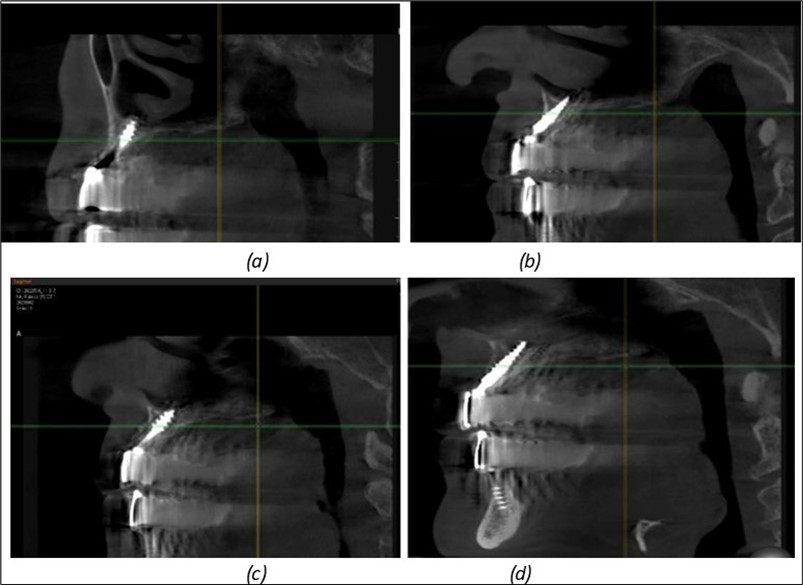

Figure 9.Implants in the pterygoid plateau area: (a) TPG implant fixed in the maxillary-sphenoid junction area, quadrant 1; (b) TPG implant fixed in the maxillary-sphenoid junction area, quadrant 2.

Figure 10.Implants in the palatal sinus cortical area to avoid bone grafting: (a) BCS implant partially fixed in the graft material mass, partially in the palatal cortex; (b) Implant fixed in the palatal cortex at the junction with the nasal cortex, behind the graft material mass.

Figure 11.Implants in the anterior area anchored in the nasal cortex (BCS and TPG): (a), (c) – BCS implants fixed in the nasal cortex; (b), (d) – TPG implants fixed in the second nasal cortex with compression in the trabecular area.

Figure 12.Implants fixed distally in quadrant 4 with fixation at the level of the mylohyoid line: (a) The most distal implant fixed in unaffected bone from the previous restoration; (b) The implant fixed in the area where the two stage implant was removed.